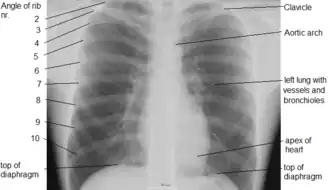

Грудна́я по́лость (лат. cavum thoracis) — анатомическое пространство, ограниченное внутренней поверхностью грудной клетки и верхней поверхностью диафрагмы. Стенки грудной полости выстилает внутригрудная фасция (лат. fascia endothoracica). Центральные отделы грудной полости заняты средостением, по бокам от которого расположены лёгкие. Лёгкие со всех сторон окружены щелевидными плевральными полостями, сформированными висцеральным (внутренним) и париетальным (наружным) листками плевры.